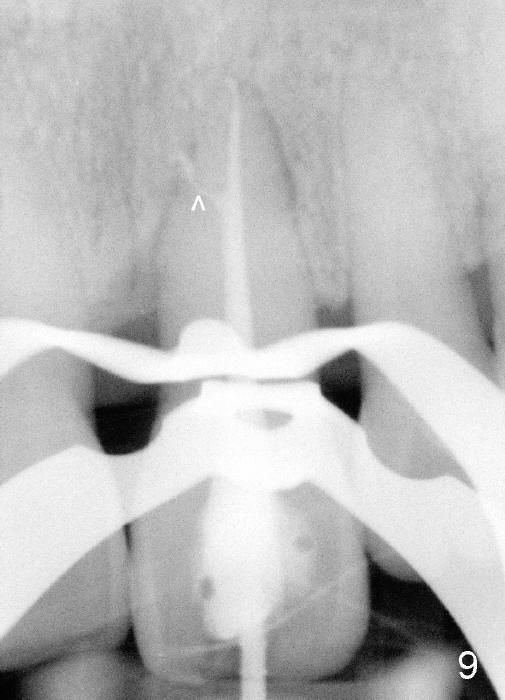

A 60-year-old lady had an abscess mesial to #9 six years ago (Fig.1,2 <), treated as a perio lesion by laser (Fig.3) and osseous surgery without bone graft (Fig.6, followed by CT exam revealing semi-circumferential bone loss (Fig.4,5). When the perio treatment failed, attention was paid to endo aspect (Fig.7-9). In fact the pulp was found to be vital when access to root canal therapy was made. As expected, the treatment failed again. The palatal fistula persisted. The infection was suspected to be a source of remote immediate implant site (#30). The tooth #9 was extracted. It appears that there is a semilunar crack line in the linguomesial root (Fig.12). When the socket healed 2 weeks post extraction (Fig.10), the #30 buccal defect was debrided with bone graft. There was no bone resorption 4 weeks post extraction (Fig.11); a 4.5x17 mm implant was placed (Fig.13-15). An immediate provisional was fabricated (Fig.16-18). Fig.19,20 were taken 3 months post implantation and 7 months post cementation, respectively. Dense bone forms around the implant coronally 4 years 5 months post cementation (Fig.21), while the gingiva is healthy palatally (Fig.22) and buccally (Fig.23).